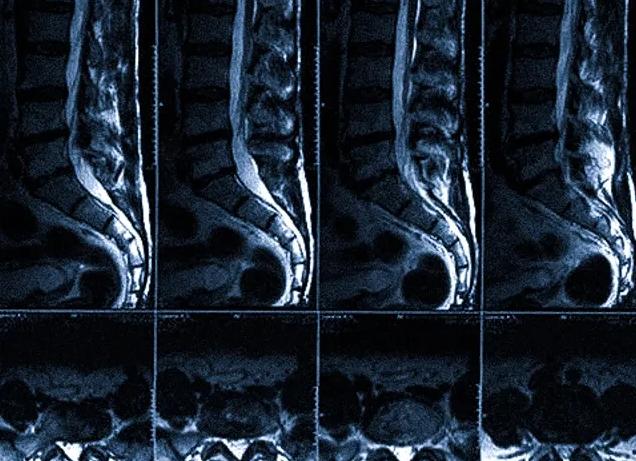

В основе любого метода визуализации лежит способность глаза отличать участки изображения по их яркости. Контрастность патологического  очага по отношению к окружающим тканям зависит от собственных свойств  ткани и способа получения  изображения на томограммах. В магнитно-резонансной томографии (МРТ) изображение, получаемое на томограммах строится на основе магнитных характеристик тканей, главные из которых — протонная плотность (р) и релаксационные времена T1 и Т2.

В большинстве случаев естественной  контрастности МР — томограмм достаточно для выявления и характеристики патологического очага. Вместе с тем встречаются ситуации, когда патологический очаг не визуализируется на томограмме вследствие изоинтенсивности или малых размеров. Бывает трудно определить границы патологических изменений при МРТ и оценить внутреннюю структуру. В таких ситуациях помогает диагностика с введением контрастных веществ, т.н. МРТ с контрастным усилением. Кроме того, есть и другие специальные применения контрастных веществ. Точкой приложения магнито-фармацевтики являются релаксационные времена. Контрастные вещества для МР исследований меняют их неспецифически и напрямую. В этом плане они принципиально отличаются от контрастных веществ, применяемых в рентгенологии, которые видны сами ввиду высокой рентгеновской плотности, поэтому, правильнее называть их контрастирующие вещества.